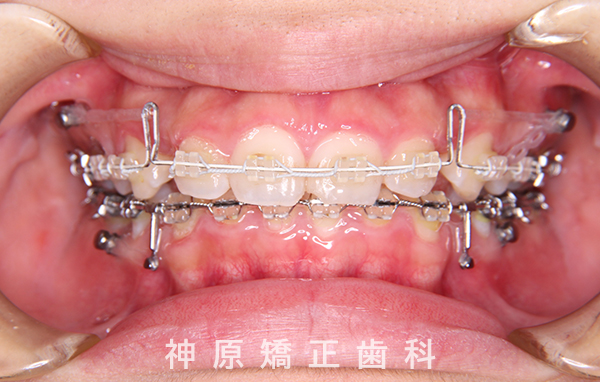

マルチブラケット装着1年後

口元の突出感を改善するために小臼歯の抜歯が必要と判断しました。抜歯スペースを活用し、前歯を可能な限り後方へ移動させるため、上下に矯正用アンカースクリューを使用する計画です。患者様とご家族に十分な説明を行い、治療ゴールに同意を得た上で矯正治療を開始しました。矯正治療の結果、側貌はE-lineに調和したバランスの良い仕上がりとなりました。